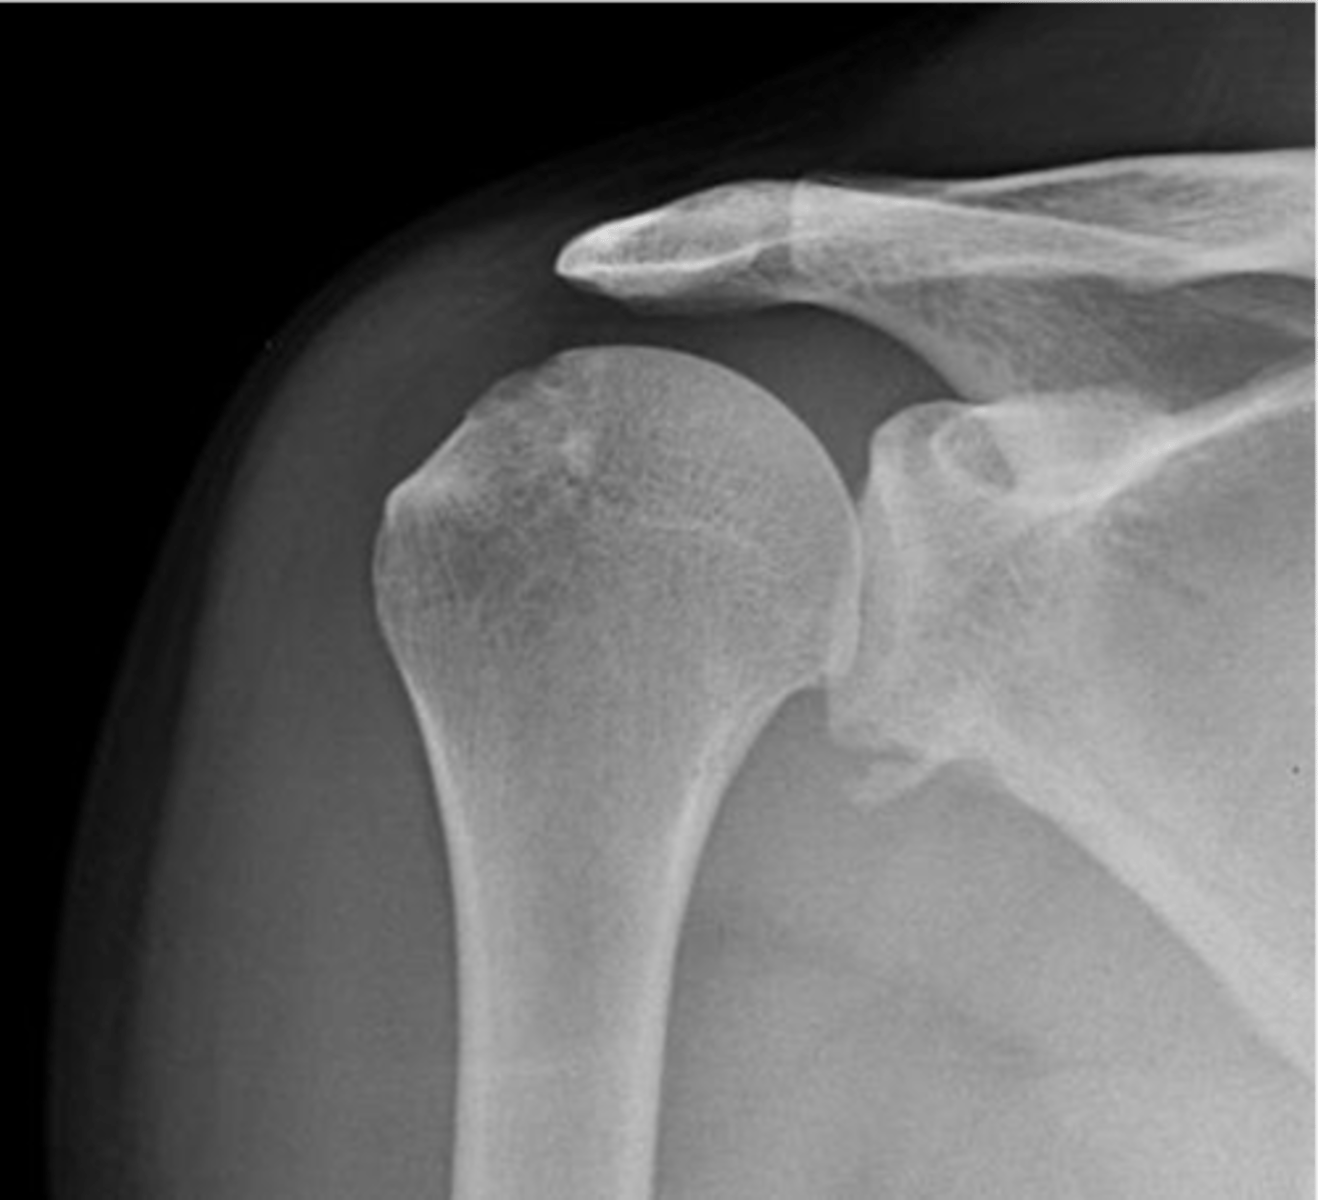

TRUE!!--we see healthy space b/w the clavicle and acromion, the humerus and the acromion, and b/w the glenoid and humerus...also, there is no sclerosing or osteophytes

True or false: this is a healthy GHJ